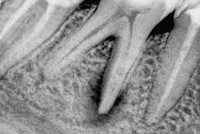

Электроодонтодиагностика при гранулирующем периодонтите выявляет увеличение порога возбудимости пульпы до 100 мкА и более. Рентгенография зуба свидетельствует о деструкции челюстной кости, а также дентина или цемента в области верхушки корня.